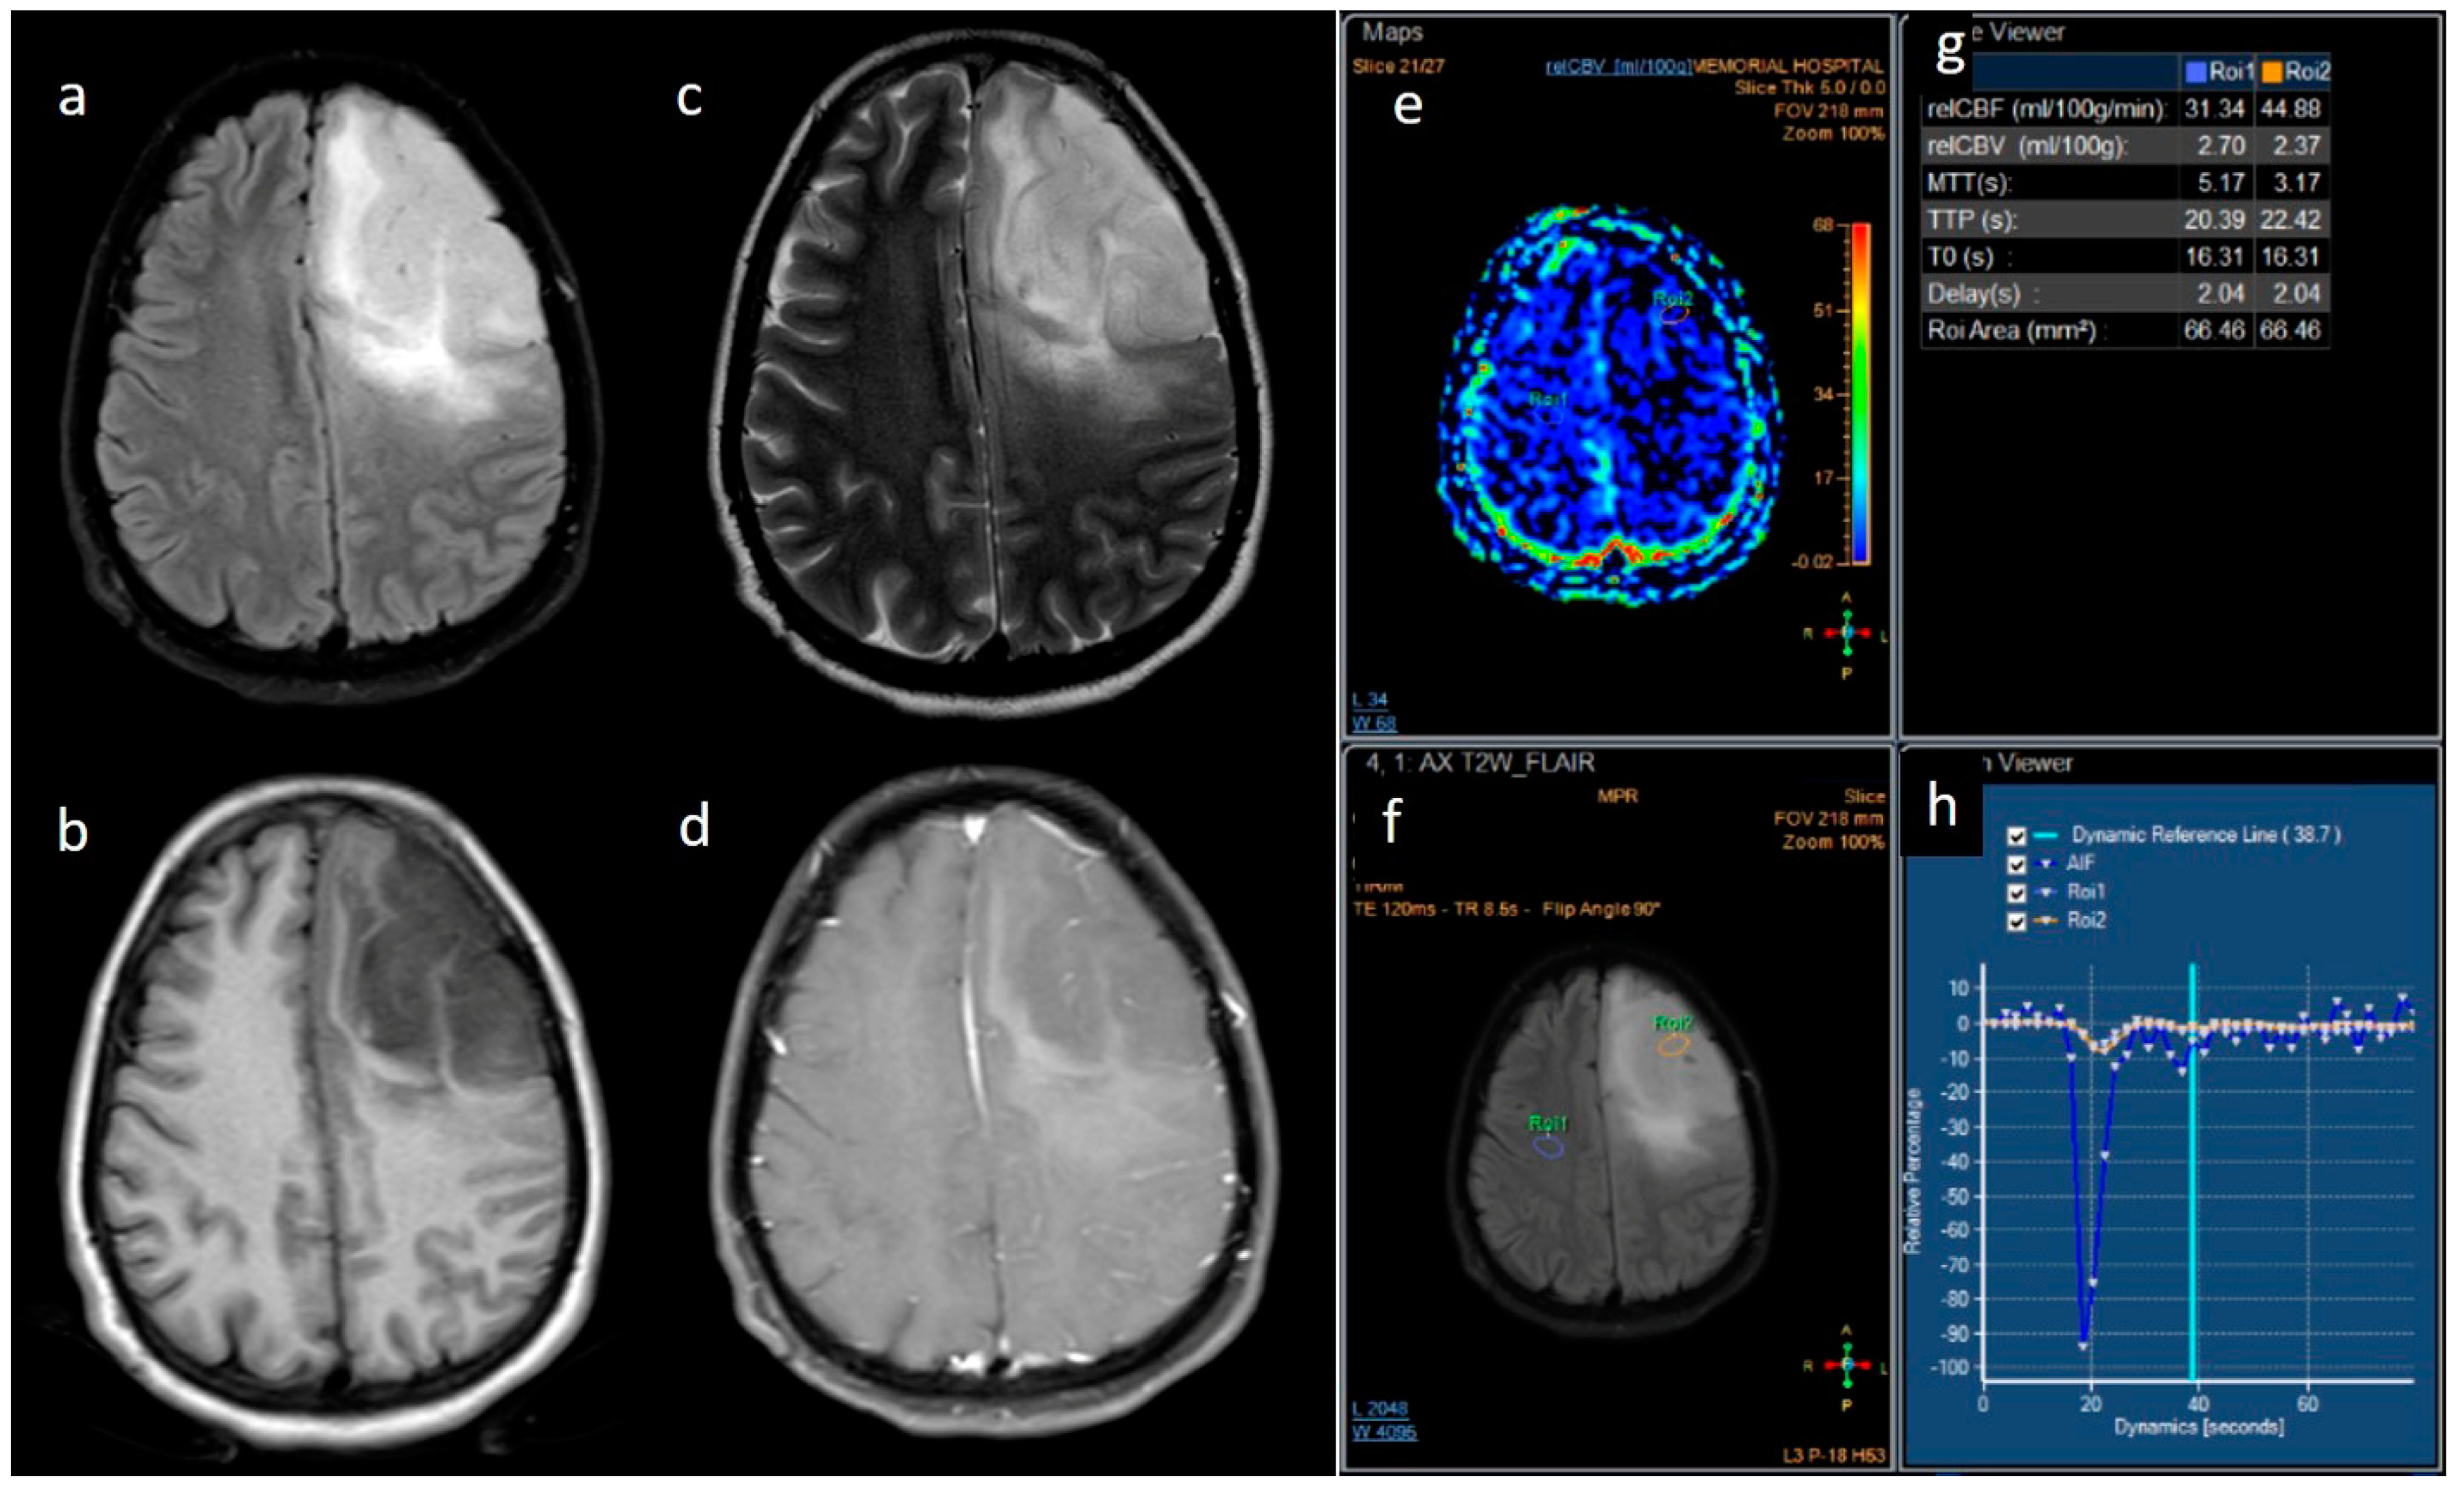

| rCBV | Median (IQR) | 1.8 [1.4–2.0] | 2.6 [1.9–3.5] | 0.001 |